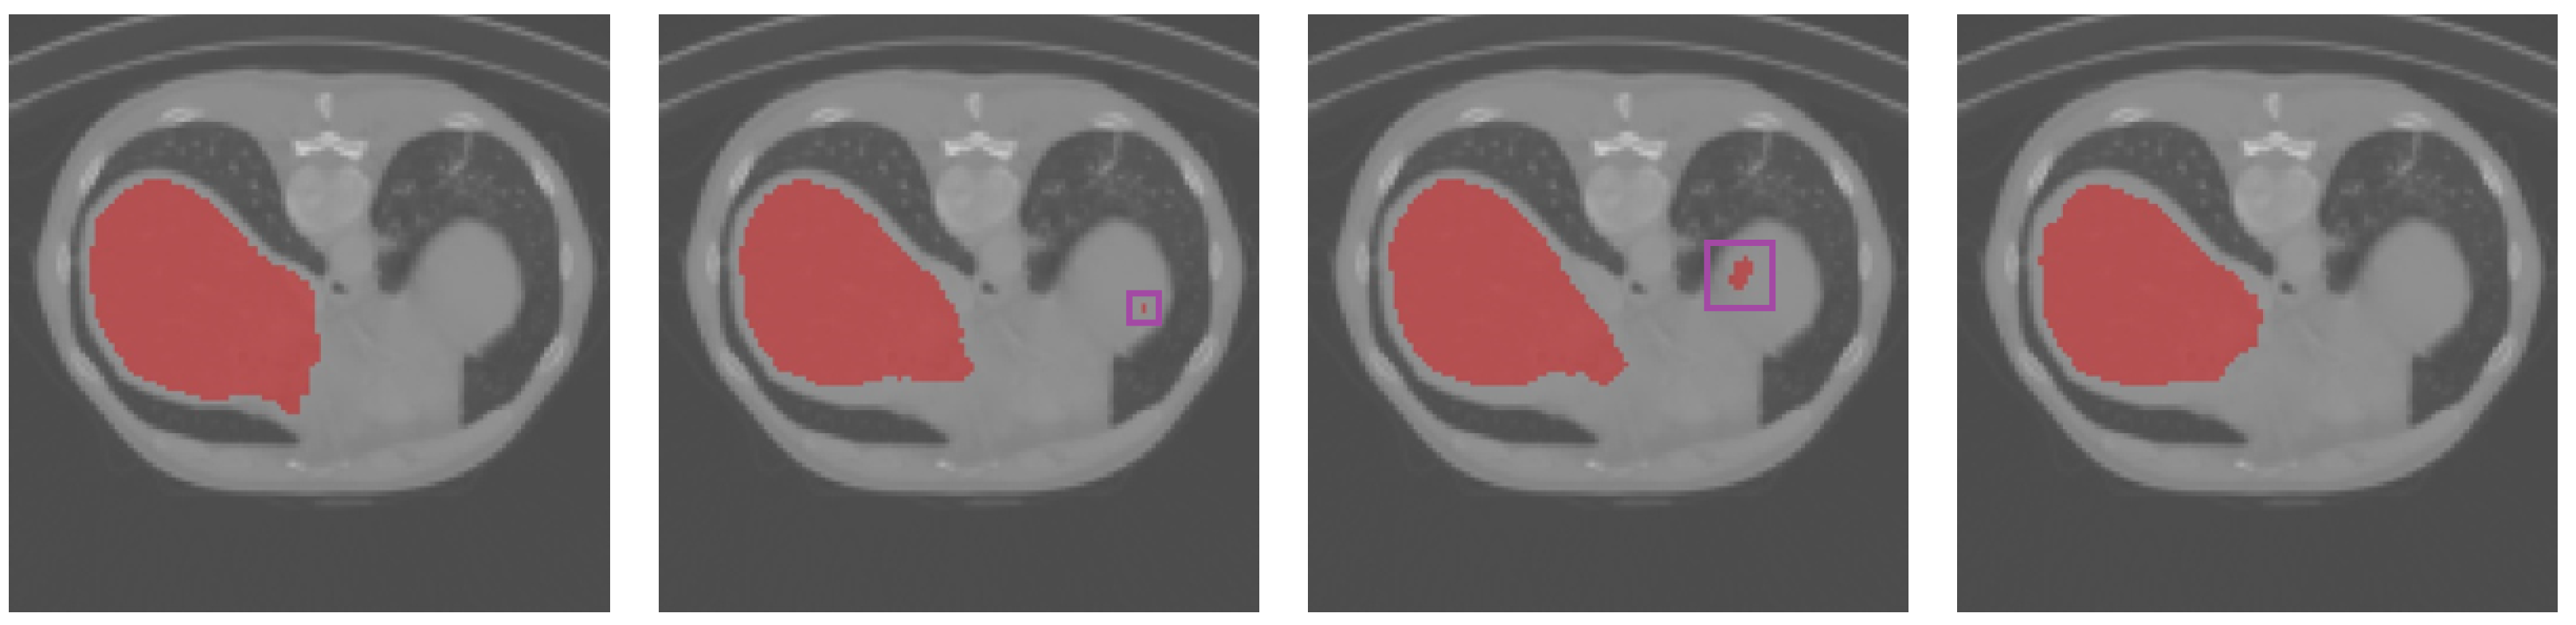

Figure 4 and Figure 5 show the results of a qualitative comparison of U-Net and Att-UNet with the proposed method, respectively. SAB-Net could capture higher semantic similarities and long-range relationships. Figure 5 demonstrates that some categories misclassified by U-Net and Att-UNet were correctly classified by our proposed method.

Figure 5.

Qualitative results obtained for the liver CT images. From left to right: ground truth, U-Net, Att-UNet, and SAB-Net.